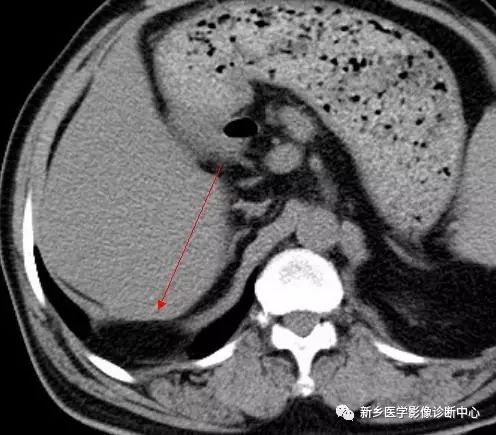

CT:贲门级部分胃体组织通过食管裂孔进入胸腔内,位于膈上,其上段食管明显扩张。

CT:食管裂孔疝以食管下端纵隔内有疝囊检出为直接征象。疝囊以假肿块样改变为特征,可有软组织密度肿块,也可表现为囊性液体密度影,部分疝囊以食管下端扩张改变为影像表现,经食管裂孔向膈下胃腔延续为主要特点。疝囊外壁光整,内壁可呈锯齿状,可见胃黏膜影像。胃壁充盈好则厚度较薄,疝囊带状管腔扩张样改变,内有潴留食物;充盈不佳者囊壁较厚,表现为软组织团块样影,内有少量液体或气体影。采用CT增强扫描,胃壁与疝囊囊壁均匀一致。

如发现疝囊壁不规则增厚,外壁不光整,周围淋巴结肿大等征象,高度怀疑食管裂孔疝合并肿瘤。需进一步胃镜活检检查。食道静脉曲张CT平扫表现为食管下端管腔轻度扩张、管壁增厚,黏膜增厚类似胃黏膜,易误诊,食道静脉曲张是肝硬化、门静脉高压的重要并发症,常与胃底静脉曲张并存;CT增强扫描显示食道下段、胃底部扩张血管影,同时有肝硬化表现,结合临床病史鉴别不难。食管下端憩室表现为囊袋状突出食管腔外的局部管腔扩张,内有气液平面,但胃腔与食管壁间无延续的胃黏膜像,且憩室下方正常食管段明显变窄,隔下有呈扩大改变的胃腔。